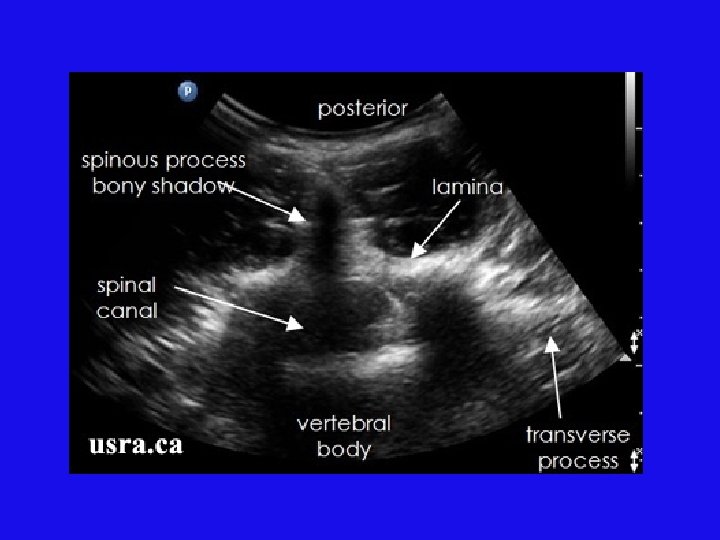

Ultrasound for spinal block placement: first, midline is marked (“shadow” of spinous processes in middle of probe). http: //www. usra. ca/sb_neuraxial

Then vertical level is marked between spinous processes, where we can see reflection from vertebral body. http: //www. usra. ca/sb_neuraxial

Ultrasound (US) can be useful in obese patients or patients with scoliosis or other spine pathology. We use the standard OB curved US probe.

Needle insertion point is intersection of midline (y-axis) and proper horizontal level (x-axis). http: //www. usra. ca/sb_neuraxial